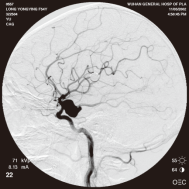

右侧颈内动脉后交通动脉瘤栓塞术前 左椎动脉造影 示左椎动脉夹层动脉瘤: 左椎动脉发出小脑后下动脉处呈囊性扩张,动脉瘤远端血管狭窄